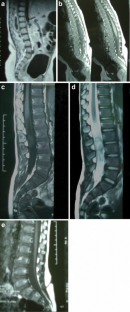

Fig. 2